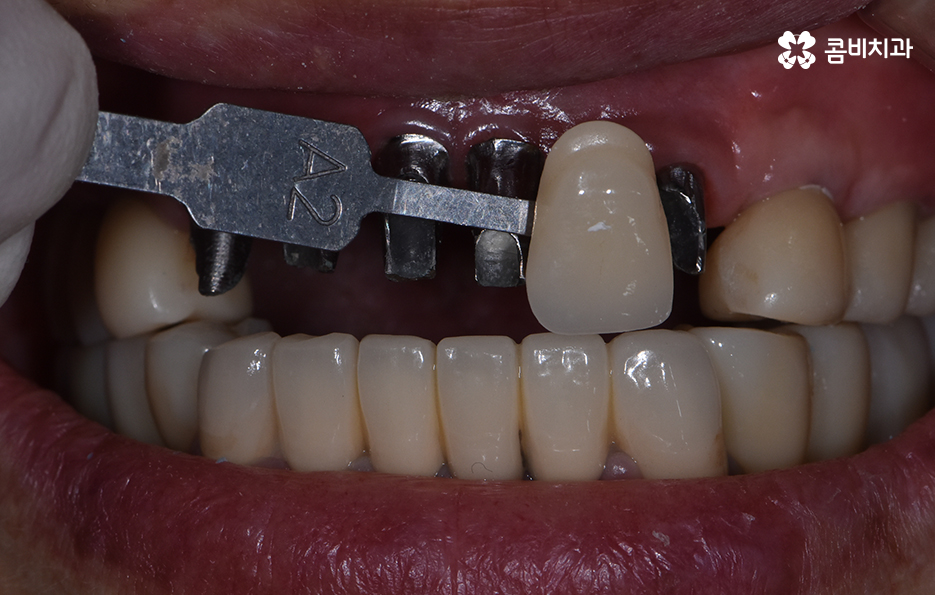

기존 치아의 색과 모양에 어울리는 보철물을 씌워서 마무리하는 과정

앞니를 잃게 되었을 때 주의해야 할 점

65세이상임플란트 기본적으로는 건강하고 안전하게

마무리가 되어야 하겠지만 앞니와 같이

평상시 대화를 할 때 주로 보이는 부위의 경우에는

심미성에 대해서 충분히 생각을 해야 합니다.

앞니는 사고로 인해서 잃게 되는 경우도 많기 때문에

젊은 분들도 잃게 되시는 경우가 종종 있는데요.

주변 치아와 비슷한 색으로 보철물을 선택하여

씌우기 때문에 시술이 끝나면 차이를 알아보기

어려울 정도로 심미적인 회복이 되는 경우가 대부분입니다.